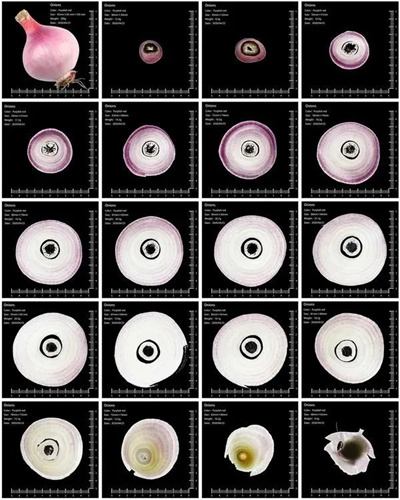

《蔬果CT》王海波 摄

创意来自于医院影像科的CT影像。一位影像科医生朋友带我检查身体,这也是我第一次做CT。检查完,在医生电脑上观察,才知道CT片拍的是横切面。走出医院,我思考怎么拍一组照片,让大家都了解CT影像。

灯椒、番茄、佛手瓜、小南瓜、藕、洋葱,我选择的这组果蔬,因为它们直径大约都在10cm左右。后期参照CT片的内容,配上文字和图表,犹如一组“蔬果CT”。